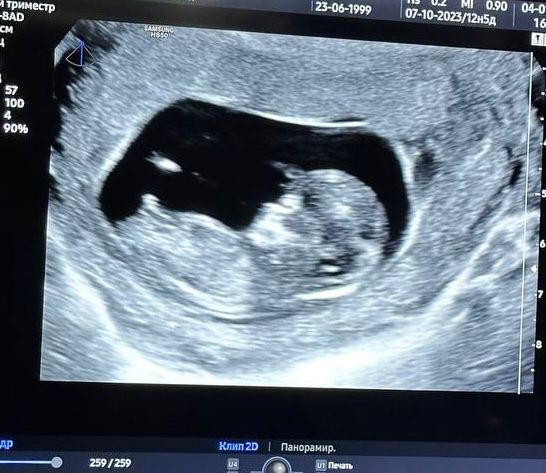

Изображение Карина, гляньте на нашу трубку😁

Ofelife, мальчик у вас, на мой взгляд) У девочек она как бы продолжая тело лежит , не торчит )

Мария, очень увлекательный аттракцион 😂 Но нам тоже кажется, что так у девочек не торчит. Все равно проверим в 16 недель )

Похоже на мальчика) У меня девочка, по-другому половой бугорок выглядел.

Изображение Вот мой "мальчик" в 16 недель, а в 20 недель мой мальчик оказался девочкой😂